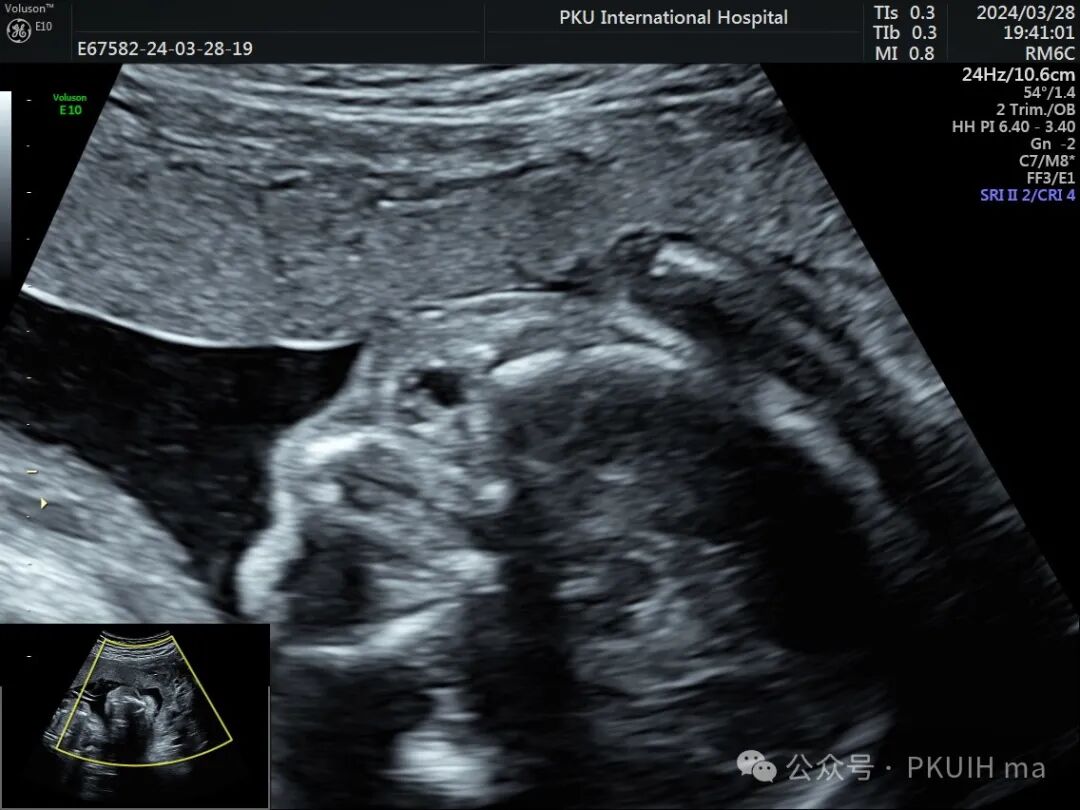

左眼发育大小正常,但晶状体边缘增厚回声也增高,应该也是有问题

双眼球对比观察两眼球发育不对称,右眼明显发育小

实时动态观察双眼发育不对称,右眼小;两侧眼球内晶状体、玻璃体均可见,右侧晶状体小,晶状体后缘玻璃体内见不规则的高回声区。

PHPV的超声表现:一侧眼球晶状体后方可见Y形高回声或强回声条带,或者是晶状体后方圆形或圆弧状高回声团块(直接征象);同时伴有患侧眼球小,晶状体形态异常,眼轴短,部分有玻璃体浑浊。双眼发病极为罕见,表现双层晶状体浑浊,内见不规则强回声或高回声带。CDFI:部分病例可见增生的玻璃体动脉内见血流信号。该病容易反复发生眼内出血,纤维血管性肿块的收缩可能对视网膜产生牵拉,导致视网膜脱离。因此,眼部超声表现可能会随着妊娠进展而改变。